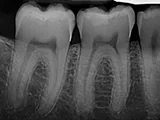

| X-Ray Example |

X-ray taken with the Schick 33 Sensor |

rec X-ray taken with the Carestream Sensor |

Dental X-Ray Comparison

X-ray taken with the Dexis™ sensorSchick

X-ray taken with the Schick® 33 sensorCarestream

X-ray taken with the Caresream® sensor